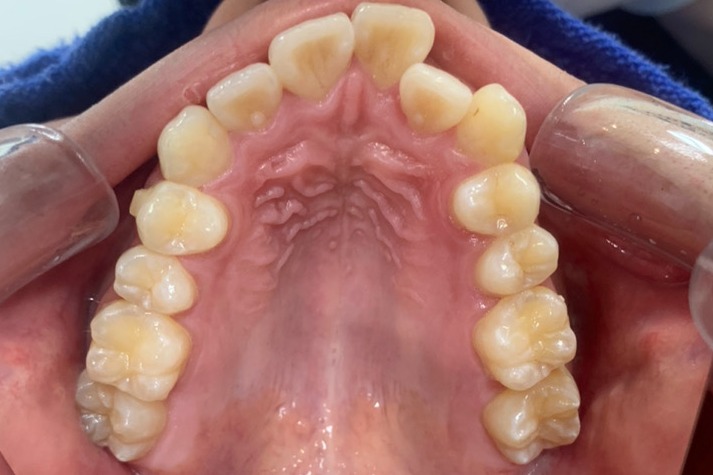

人と接する機会が多く、第一印象を大切にしたいと考え、写真写りや笑顔への自信を高めたいという思いから矯正を決意された矯正当時学生だった22歳男性の H.S.様に、スマイルモア矯正を選んだ理由を伺いました。

| 費用 | 360,000円(税込396,000円) |

| 治療期間 | 11ヶ月 |

| 治療内容 | マウスピースを用いた歯列矯正 |

| 追加処置 | IPR |

以前よりも歯並びが改善され、人とコミュニケーションをとることに自信がつきました。 「スマイルモア」という名前の通り、笑顔に自信がついたことで今までよりも口を開けて笑う機会も増えました。 矯正期間が年単位だったのですぐに変化があったわけではないですが、綺麗な仕上がりに満足しています。